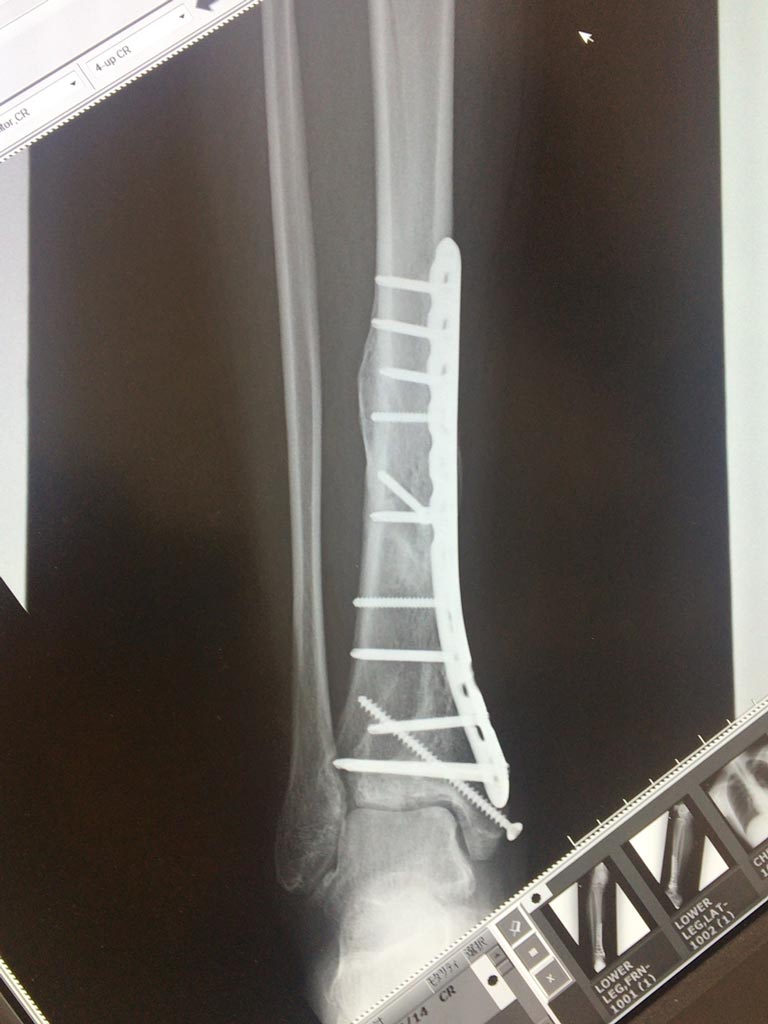

手術直後と退院する時のレントゲンを見比べても全然判らなかったけど、今回は素人目に見てもガッツリ骨がくっついてるのが見て取れて、だいぶテンションを上げ過ぎて『ちょっ!先生これちょっと写真撮って良いっすか写真!?』とか一人でキャッキャしてたら先生に笑われたf(^_^;)

あ、手術直後のレントゲンはこんなです。

粉々になった部分ほど密度が上がってるように見えるし、なんかエラいモリモリ盛り上がってるところとかあって、骨って樹木みたいですよね(笑)